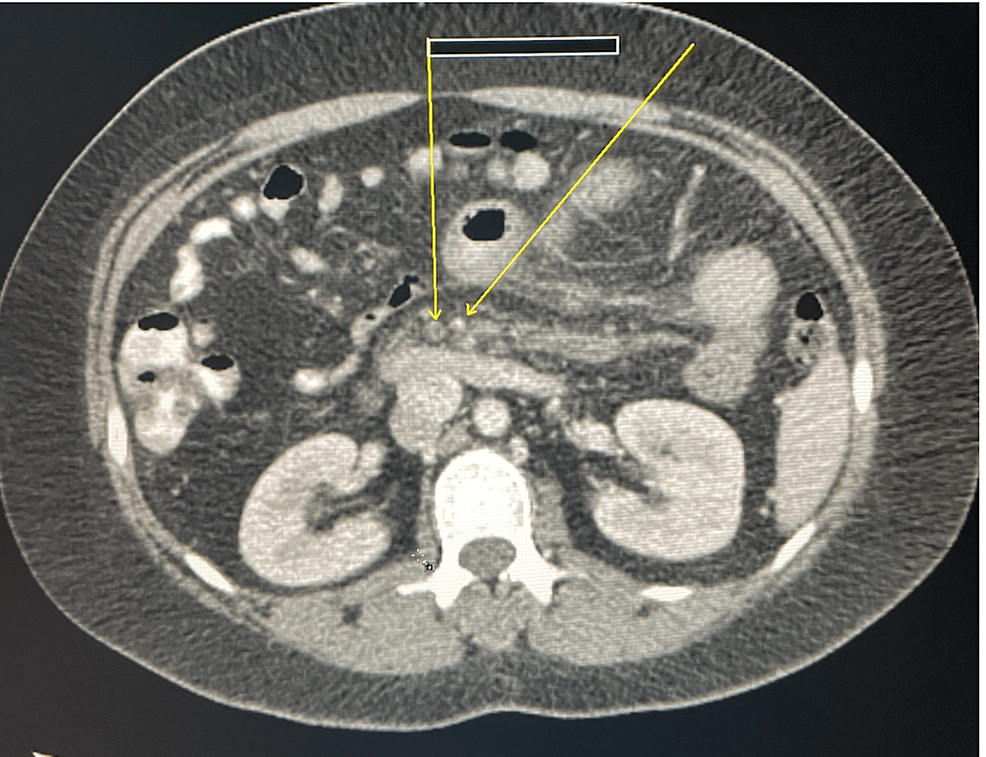

From www.cureus.com

Cureus Acute Portal Vein Thrombosis as an Initial Presentation of Doac Use In Protein C Deficiency for protein c deficiency, the published clinical experience on doac use was generally in line with our results, with. this topic review discusses the diagnosis and management of protein c deficiency (inherited and acquired). in this prospective cohort study, we aimed to evaluate the efficacy and safety of direct oral anticoagulants. Few studies have evaluated the use. Doac Use In Protein C Deficiency.